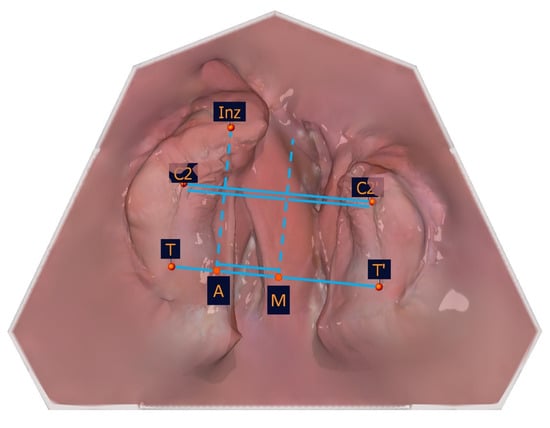

The transversal measurements are shown in Table 5 and in Figure 10.

Figure 10. Illustration of the transversal measurements.